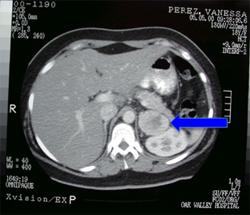

- Tomografia komputerowa (CT): Pozwala na dokładne określenie lokalizacji, rozmiaru oraz cech morfologicznych guza, co umożliwia przeprowadzenie oceny przedoperacyjnej i monitorowanie zmian w czasie.

- Rezonans magnetyczny (MRI): Zapewnia szczegółowe obrazy strukturalne guza i otaczających tkanek, co może być przydatne w planowaniu operacji chirurgicznej oraz ocenie potencjalnego zaangażowania okolicznych struktur.